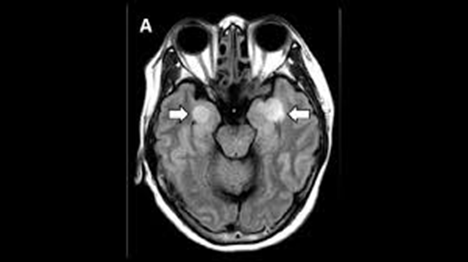

RADIOLOGICAL IMAGING

Radiological image helps to detect various abnormality of brain. CT (Computed Tomography) scan, MRI (Magnetic Resonance Imaging) is use to detect various structural abnormality (Like: cell damage, tumour, internal bleeding, stroke) in entire cranial vault such as cerebrum, brainstem, cerebellum etc. But it can’t detect presence of any microorganism like; N. fowleri directly. When the amoeba spread accurately it will detect what kind of damage does the amoeba cause brain cell.(19)

With the CT (Computed Tomography) scan it show normal report on the early stage of scanning, and into the growing stage or moderate it shows some default like diffusion in cerebral edema, hypodense in frontal and temporal lobes areas, decreasing in the Gray-white matter, into the advance stage it show excessive brain swelling and also show brain herniation. That helps us to detect infection in brain cell.

In case of MRI (Magnetic Resonance Imaging) it’s produced better analysis respected to CT scan. It’s helps us by detecting Hypointense/isointense lesions through T1-weighted imaging, hyperintense signals from frontal, temporal lobes through T2-weighted imaging, cytotoxic edema through diffusion-weighted imaging.

Although radiological imaging does not directly helps us to detect N. fowleri amoeba. But still it’s easily available less time consuming and help us to know brain morphological condition.

FIG 6 – MRI IMAGE SHOWING N. FOWLERI